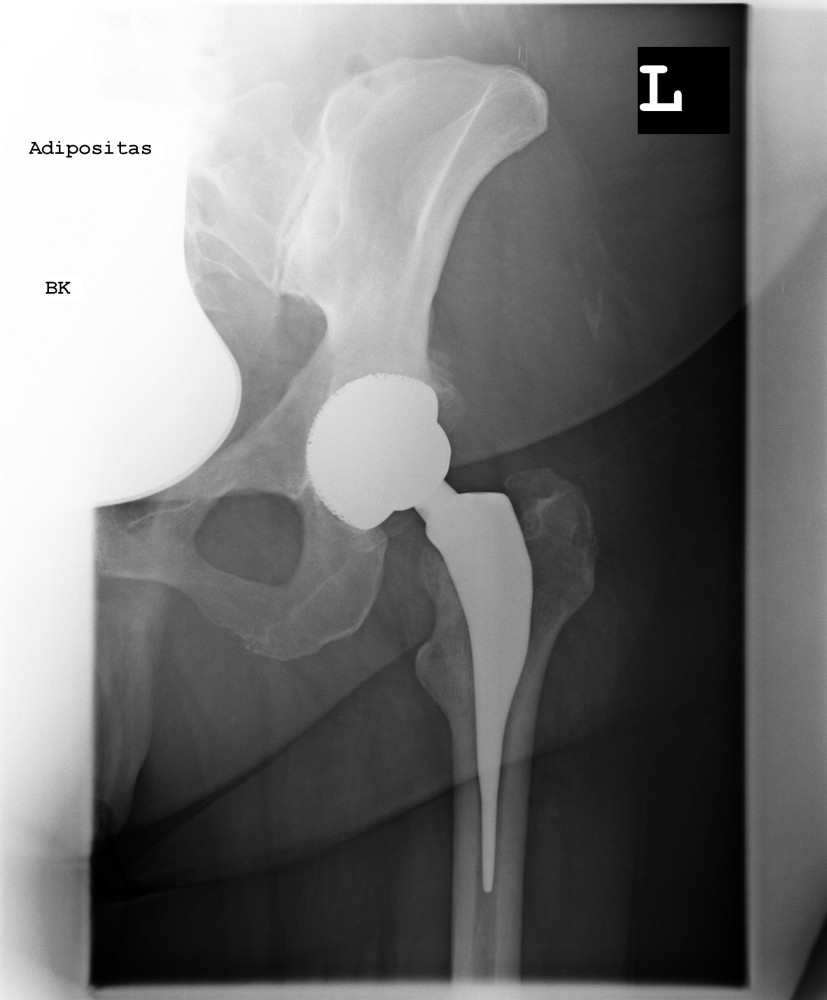

Kurzschaftprothese

Ziel einer Endoprothese ist es bei der Implantation möglichst viel Knochen zu erhalten. Somit wurden in den letzten Jahrzehnten Prothesenmodelle entwickelt, die aufgrund Ihres Designs eine optimale Krafteinleitung in den Knochen bei maximalen Knochenerhalt gewährleisten. Bei diesen sogenannten Kurzschaftprothesen wird außerdem die Biomechanik des Gelenkes kaum verändert. Dies hat zur Folge dass Sie das Implantat kaum noch bis gar nicht „spüren“.